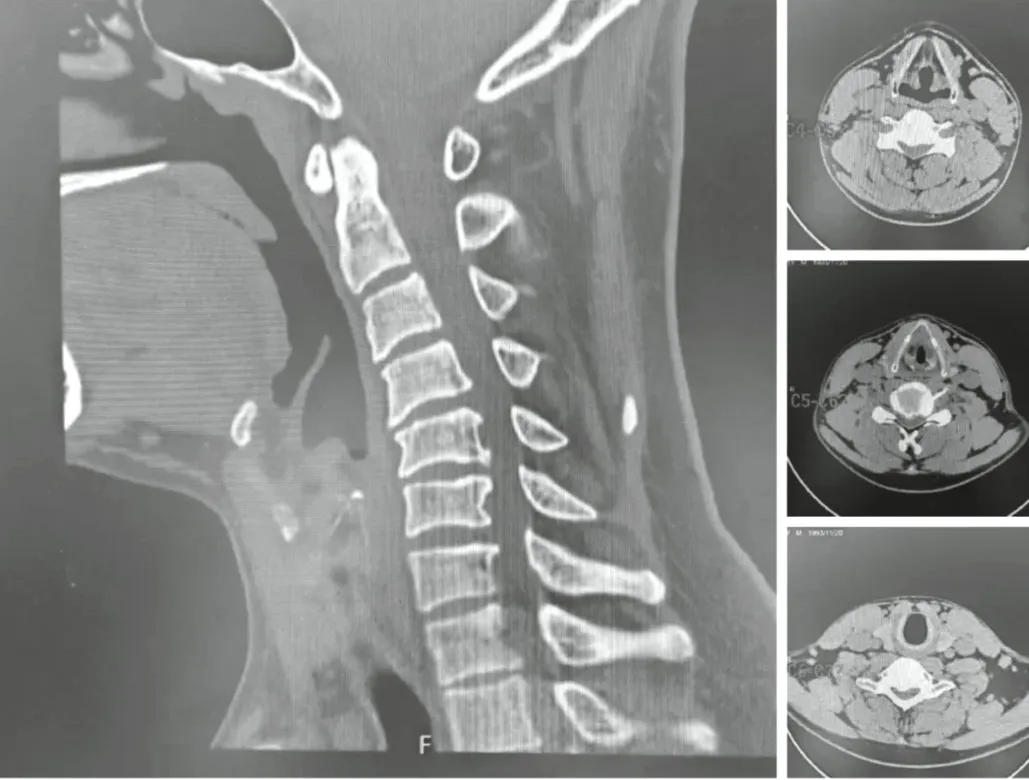

入院前,许先生心里嘀咕:有没有不开大刀,微创治疗自己颈椎病的手术方式?针对许先生的病情,脊柱外科技术主任李茂廷和常帅联合查房后,组织脊柱团队进行病例分析和术前讨论,由于病人的颈椎CT未见明显的后纵韧带骨化(图2所示),决定按照“个体化、精准化、微创化”的治疗理念,采用新型的单通道软质内镜(LUSE)技术来辅助完成此例颈椎前路三节段ACDF手术。

图2,颈椎CT:未见明显后纵韧带骨化。